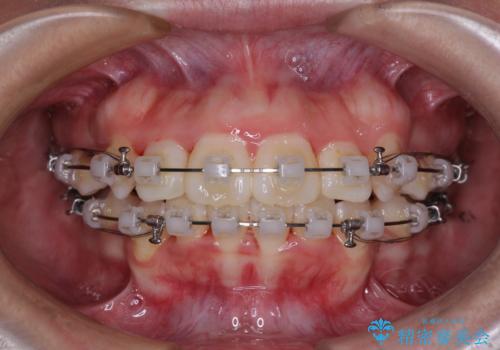

唇からはみ出るほど飛び出した前歯 ワイヤー装置による抜歯矯正

- クリアブラケット

- 2年

- 飛び出した上顎の前歯と八重歯を気にして来院された患者様です。

口元を積極的に引っ込めるために、上下左右の小臼歯計4本を抜歯することとしました。

舌の突出癖が強いため、しっかりと口元を引っ込めるため、舌のトレーニングをしっかりと行いながら矯正治療を行うこととしました。